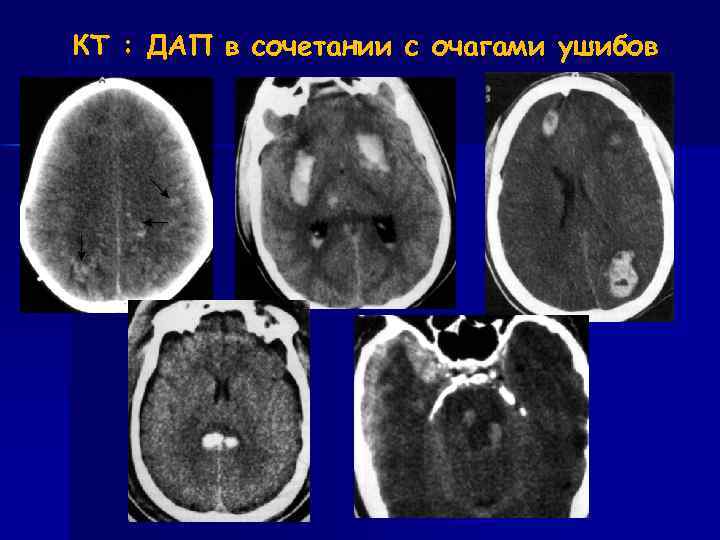

Первичные повреждения Диффузное аксональное повреждение (ДАП) Механизм – ускорение / торможение, ротация Локализация – полушария головного мозга - граница серого и белого вещества - лобные и теменные доли (50%) - базальные ганглии - мозолистое тело (валик) - средний мозг (дорсальные отделы) Диагностика: - КТ информативна только в 10% случаев. - МРТ ≈ 93%

КТ : ДАП в сочетании с очагами ушибов